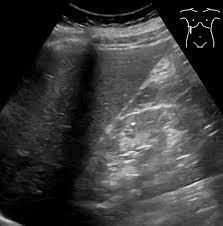

복부 초음파는 초음파(ultrasound)를 이용해 복부 내 장기들의 상태를 확인하는 비침습적 검사 방법입니다. 방사선을 사용하지 않아 인체에 해롭지 않고, 고통 없이 실시간으로 복부 장기들을 관찰할 수 있다는 점에서 가장 기본적이면서도 효과적인 진단도구로 평가받습니다.

초음파 탐촉자(Probe)에서 발생한 고주파 음파가 인체 내부 장기에 부딪혀 반사되며, 복부 초음파로 알 수 있는 것은 바로 이 반사파를 영상화해 간, 담낭, 췌장, 비장, 신장(콩팥), 방광, 대동맥, 림프절 등의 상태를 분석하게 됩니다.

담낭 및 담도 질환

- 담석증

- 담낭염

- 담낭 용종

- 담도 폐쇄

- 담낭암